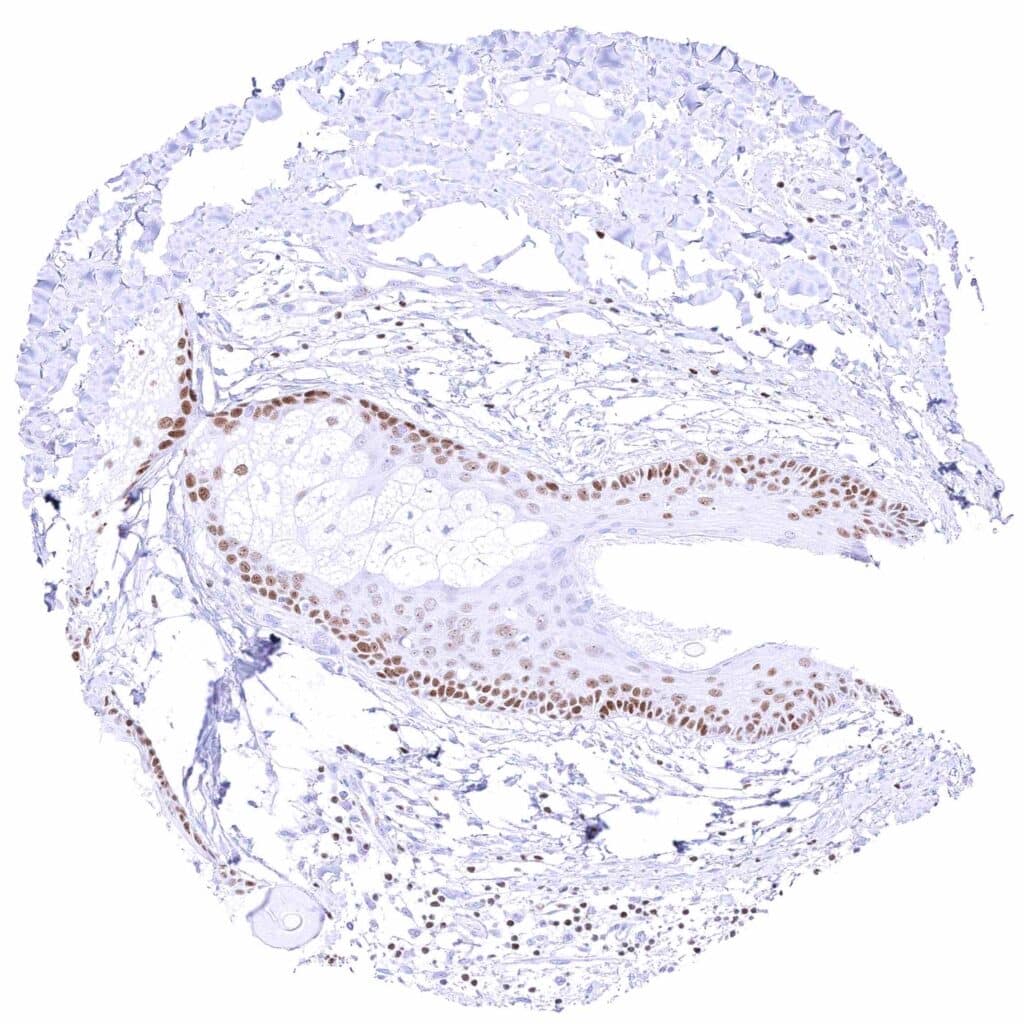

Breast – Moderate to strong GATA3 staining of luminal cells while myoepithelial cells remain GATA3 negative.